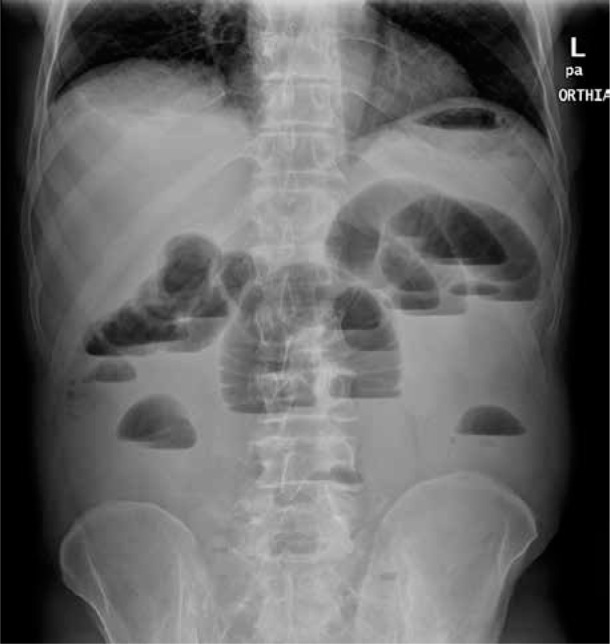

A case report of an idiopathic adult ileocolic intussusception.

特发性成人回结肠肠套叠病例报告。